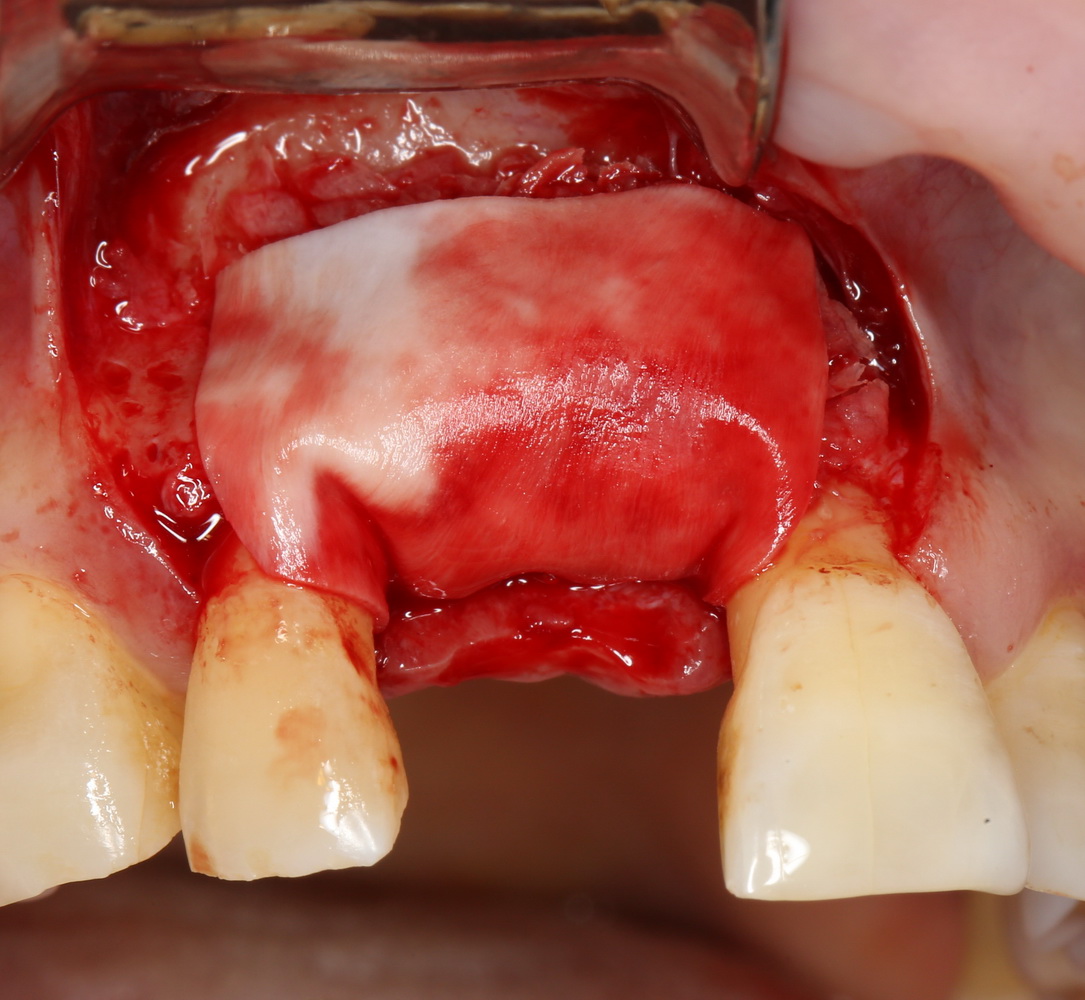

Поэтому мы используем мембрану Geistlich BioGide и всё ту же аутокостную стружку:

Вот чем мне нравится мембрана BioGide — так это своими свойствами. Предсказуема до мелочей.

Во влажном состоянии она эластична и податлива, поэтому нет необходимости использовать пины или винты:

ну и, швы: